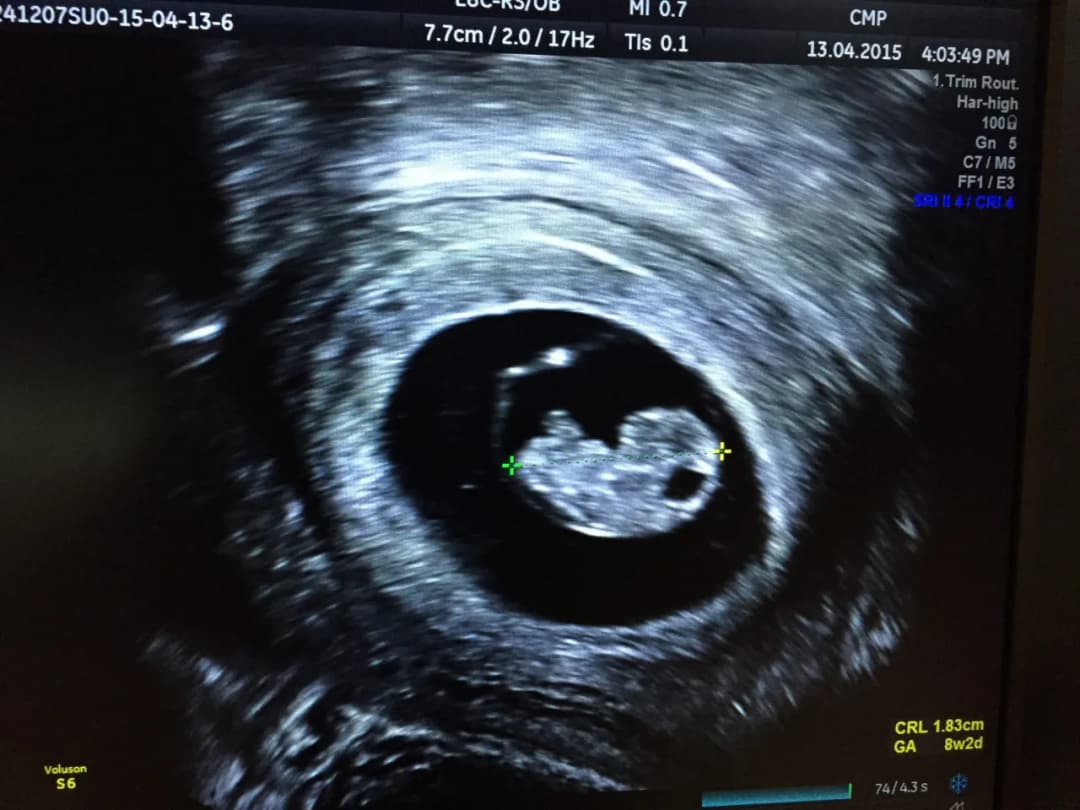

Pęcherzyk żółtkowy w USG - jak prawidłowo powinien wyglądać w kolejnych tygodniach ciąży? Wielkość, kształt, położenie, zmiany niepokojące. Porady ekspertów i przydatna wiedza dla przyszłych mam.